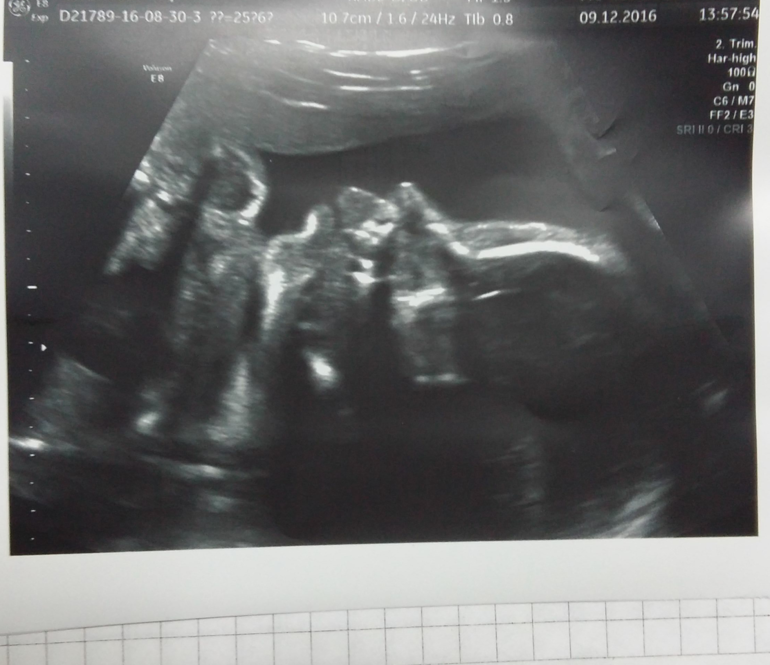

Сходили мы на узи в 26 неделек

УЗИ, КТГ, доплерСлава Богу все у нас хорошо!! Растем. Весим уже 800гр)

Плацента 1 ст зрелости и 29 мм Это хорошо? Под кат результаты

Плацента хорошая. И все в норме!😊 Сейчас посмотрела свое УЗИ на этом сроке. Все показатели у нас близки.